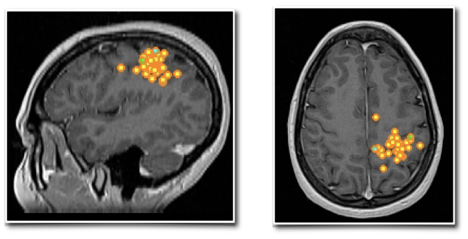

下图清晰显示了琳娜在Rolandic区(中央区)出现的棘波簇(图中黄色点状信号带橙色轮廓):左图为矢状位视图,右图为轴位视图。这一定位不仅揭示了致痫病灶所在,更明确了其与关键脑功能区之间的毗邻关系,为后续手术提供了精确的导航依据。

脑磁图(MEG)显示中央区棘波簇的矢状位与轴位视图